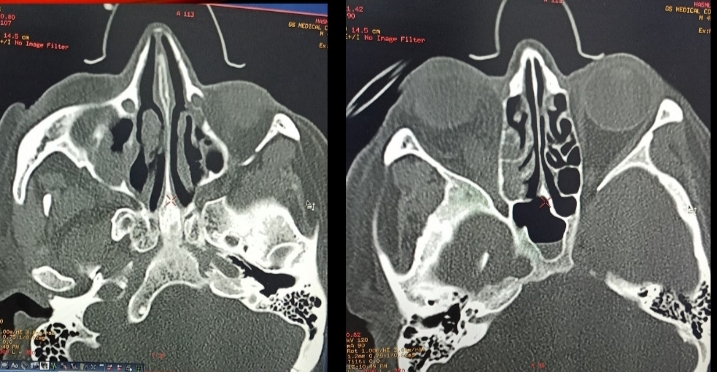

Image 1.2 Computerised tomography. a. Rt maxillary sinus non-hemogenous opacification, b. Rt orbital involvement with proptosis.